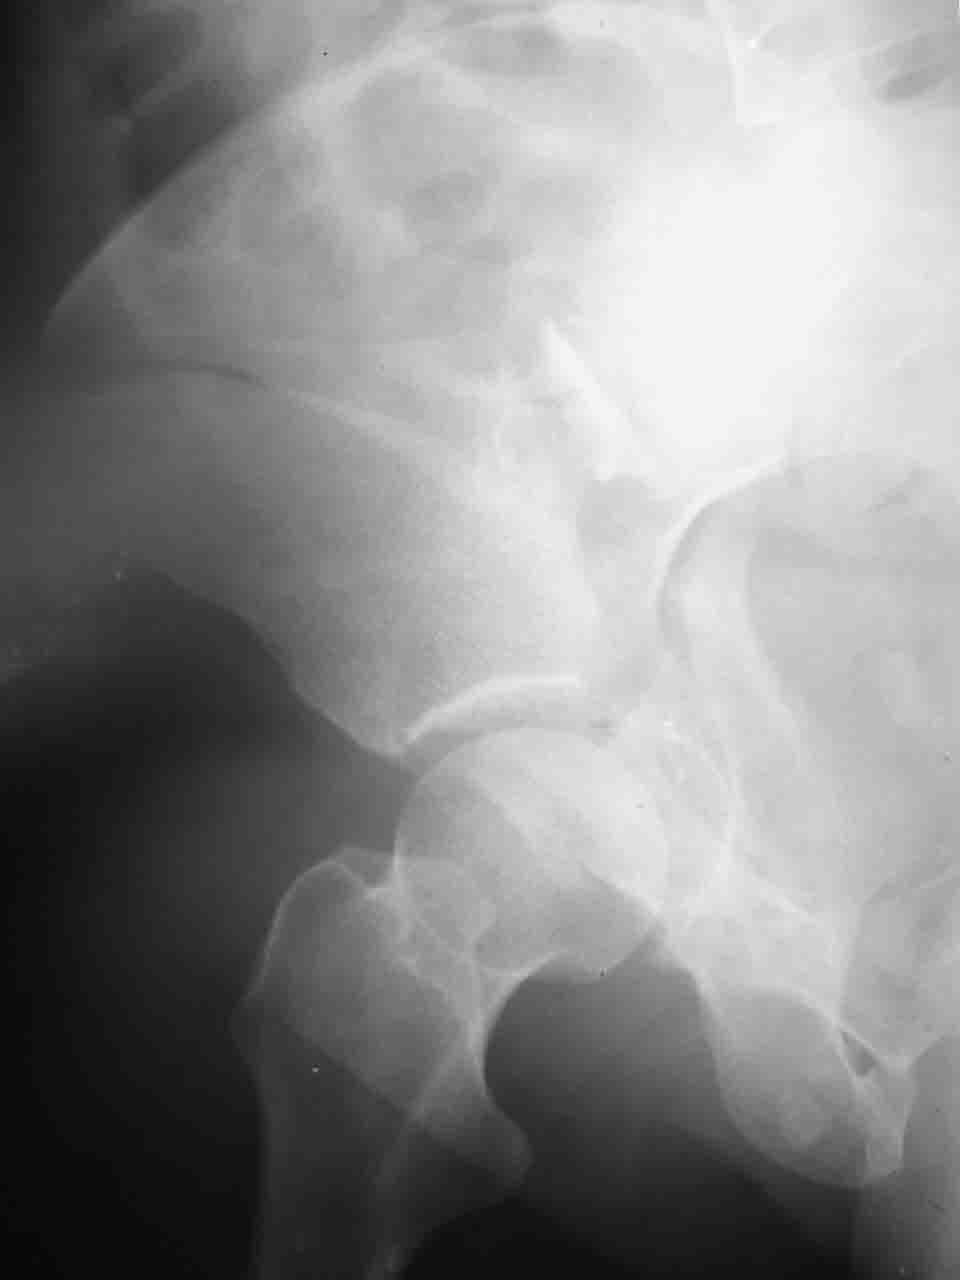

А какой отдел вертлужной впадины более важен передний или задний? Чем был обусловлен выбор доступа к суставу? Проще говоря, почему вы пошли передним доступом на двухколонный перелом? Мне понятны ваши сомнения, когда не удется сделать все что хотелось бы. В данном случае доступ должен быть чрезвертельным боковым (как и советовал Рунков) или двумя доступами.

Логика подсказывает, что все-таки лучше иметь анатомически полноценную впадину, хотя ранее упоминалось состояние вторичной конгруэнтности и одно наблюдение у меня есть, когда у больного с полностью нарушенной анатомией впадины и подвывихом головки бедра кзади и кверху боли отсутствовали при относительно достаточном для стиля жизни больного объёме движений. Но это только одно наблюдение и кроме перелома впадины у этогобольного была и тяжелая ЧМТ в анамнезе. Основываясь на формулировке структуры ацетабулюм Э. Летурнеля - как перевернутой буквы Y, впадина для полноценной функции сустава должна иметь сферичность, соответствующую размеру головки бедра и если один из компонентов в дефиците, то функциональные последствия рано или поздно проявятся.

Сложностью, ассоциативностью характера перелома, я бы с радостью воспользовался мининвазивной перкутанной фиксацией винтами, но боюсь, что результат был бы ещё хуже, техникой непрямой репозиции перелома не владею, поэтому пытаясь получить анатомичную впадину приходится широко открывать, по крайней мере пока, а дальше буду пытаться уменьшать пространство...

Илеофеморальный доступ не совсем передний и сравнительно с илеоингвинальным, и Кохера-Лангенбека открывает весь наружный таз кроме самых передних отделов лонных костей, фиксацию которых я не ставил в задачу. Обширность диссекции, большая длительность операции и более высокий риск гетерооссификации - отрицательные моменты в обмен на возможность легче ориентироваться.

Вопрос доступа к вертлужной впадине при остеосинтезе задача не простая. Конечно, у Летурнеля и Тайла всё давно описано, нам остается только брать на вооружение. Но сами понимаете, что не бывает двух одинаковых ситуаций, поэтому в каждом случае вопрос решается сугубо индивидуально. Наша главная цель - восстановить анатомию с нанесением минимальной дополнительной травмы тазобедреннному суставу, думаю с этим никто не поспорит. Расширенный илиофеморальный доступ уж слишком травматичен (как сказал один коллега "таз лежит отдельно, больной отдельно").Стоит ли делать из пациента анатомический препарат для того чтобы легче ориентироваться. Да и нужно ли собирать всю "мозаику"? Мы применяли при таких операциях своеобразную операционную хитрость - сначала устраняли грубое смещение крыла под гребнем с фиксацией так называемой "плавающей" пластиной (временно фиксированной на двух винтах)- доступ или продлевали боковой, или делали небольшой дополнительный разрез над гребнем. Это позволяло устранить грубое смещение и захождение отломков тела повздошной кости, что значительно облегчало репозицию и остеосинтез впадины над сводом. Основное внимание конечно же уделяли нагружаемому задне-верхнему отделу. Сообщите ваш адрес, пришлю схемы и рентгенограммы.